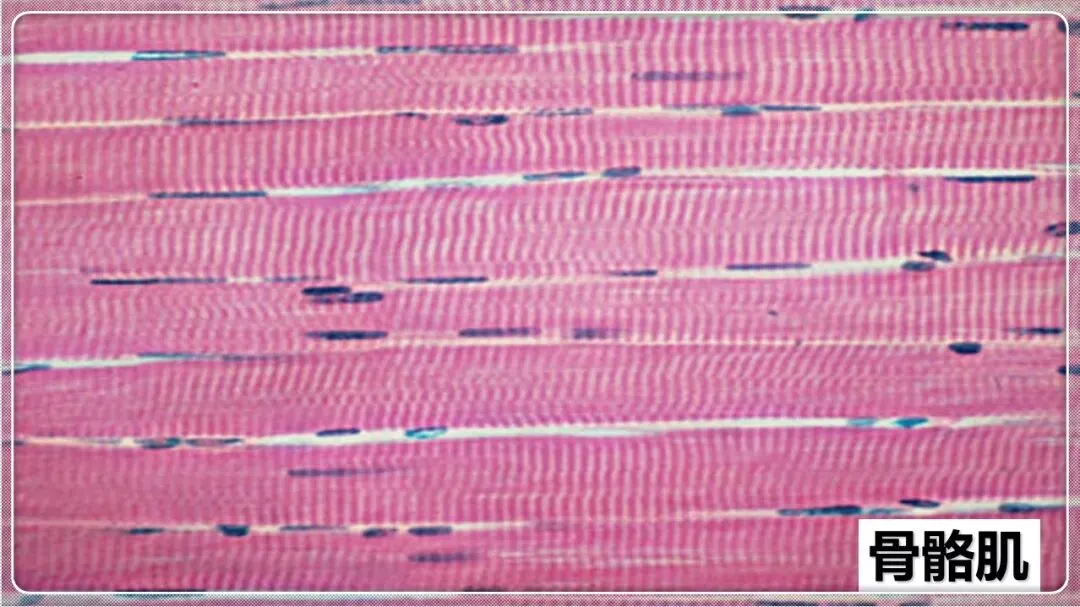

组织学与胚胎学笔记pdf【 常考图谱】

组织学与胚胎学 图谱